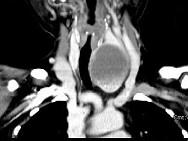

问题 女,56岁,发现颈部肿块1月余,CT如图所示,最可能诊断为()

选项 A.甲状舌管囊肿 B.甲状腺乳头状癌 C.甲状腺原发淋巴瘤 D.甲状腺腺瘤 E.甲状腺脓肿

答案 D